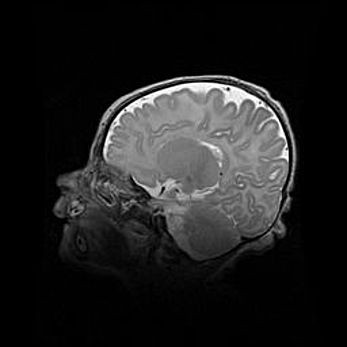

Неполная лизэнцефалия (пахигирия). Открытая гидроцефалия.

Возраст: 17 дней

Вес: 3110 г

Пол: мужской

Окружность головы: 33,5 см

Срок гестации: 35-36 недель

Лизэнцефалия—недоразвитие корковой пластинки и мозговых извилин в результате нарушения миграции нейронов коры. Поверхность мозговых полушарий гладкая. Микроскопически выявляется отсутствие нормальных слоев коры и скопление групп нейронов в подкорковом белом веществе.

Пахигирия—уменьшение числа вторичных извилин. В пораженном полушарии нервные клетки образуют толстый недифференцированный слой с неправильно расположенными нервными волокнами и группами гетеротопных клеток. Нервные клетки незрелые. Белое вещество истончено. При этом нередко аномально развит корково-спинномозговой путь.